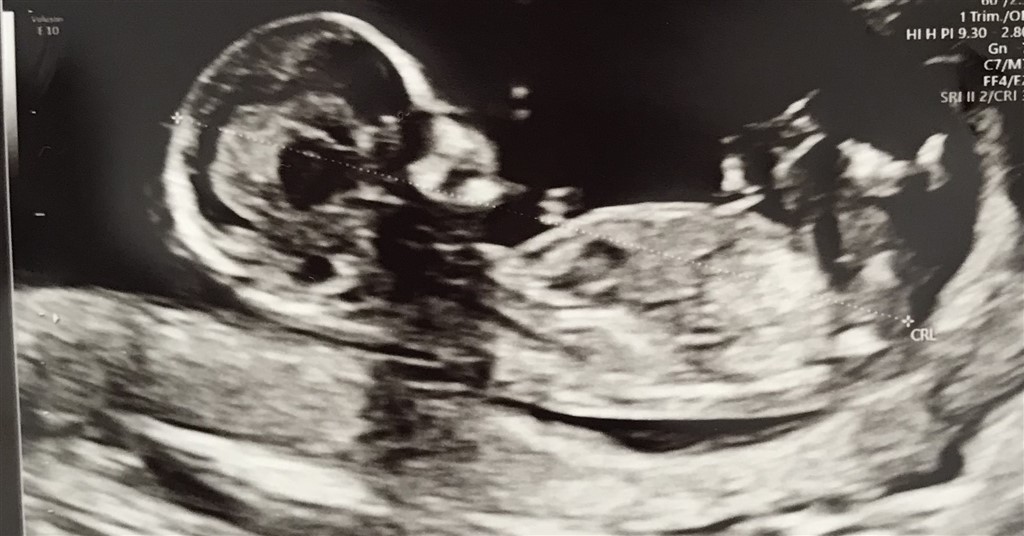

Hejsa piger. Jeg er 12+5 og har set herinde at nogen via nubteorien gætter kønnet. Har I lyst til give jeres bud. Knus

Jeg gætter på en pige

Mit umiddelbare bud er en pige